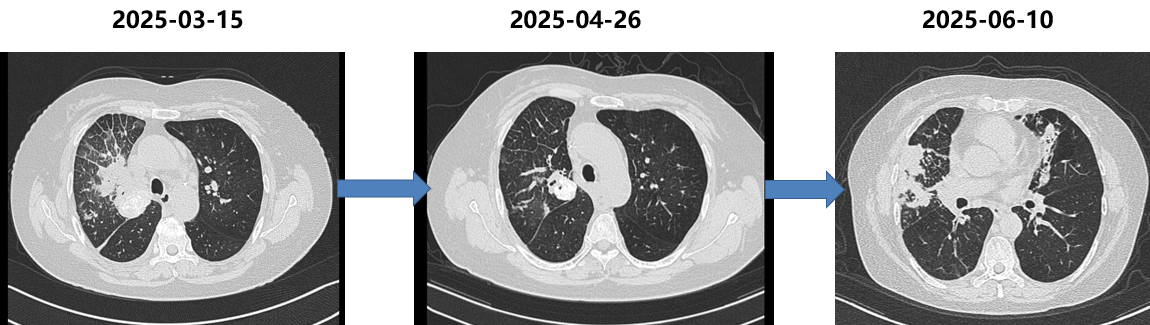

四线治疗(2025-04至2025-06)

依据:病理证实转化为SCLC。

方案:依托泊苷+顺铂,共4周期。

PFS:3个月。

胸部CT(2025-06-10):病灶再次快速进展。

五线治疗(2025-06至今)

依据:SCLC后线治疗,DLL3靶点药物。

方案:塔拉妥单抗1mg D1,10mg D8,D15(阶梯给药)。

PFS:3个月

胸部CT(2025-09-24):病灶再次出现进展。